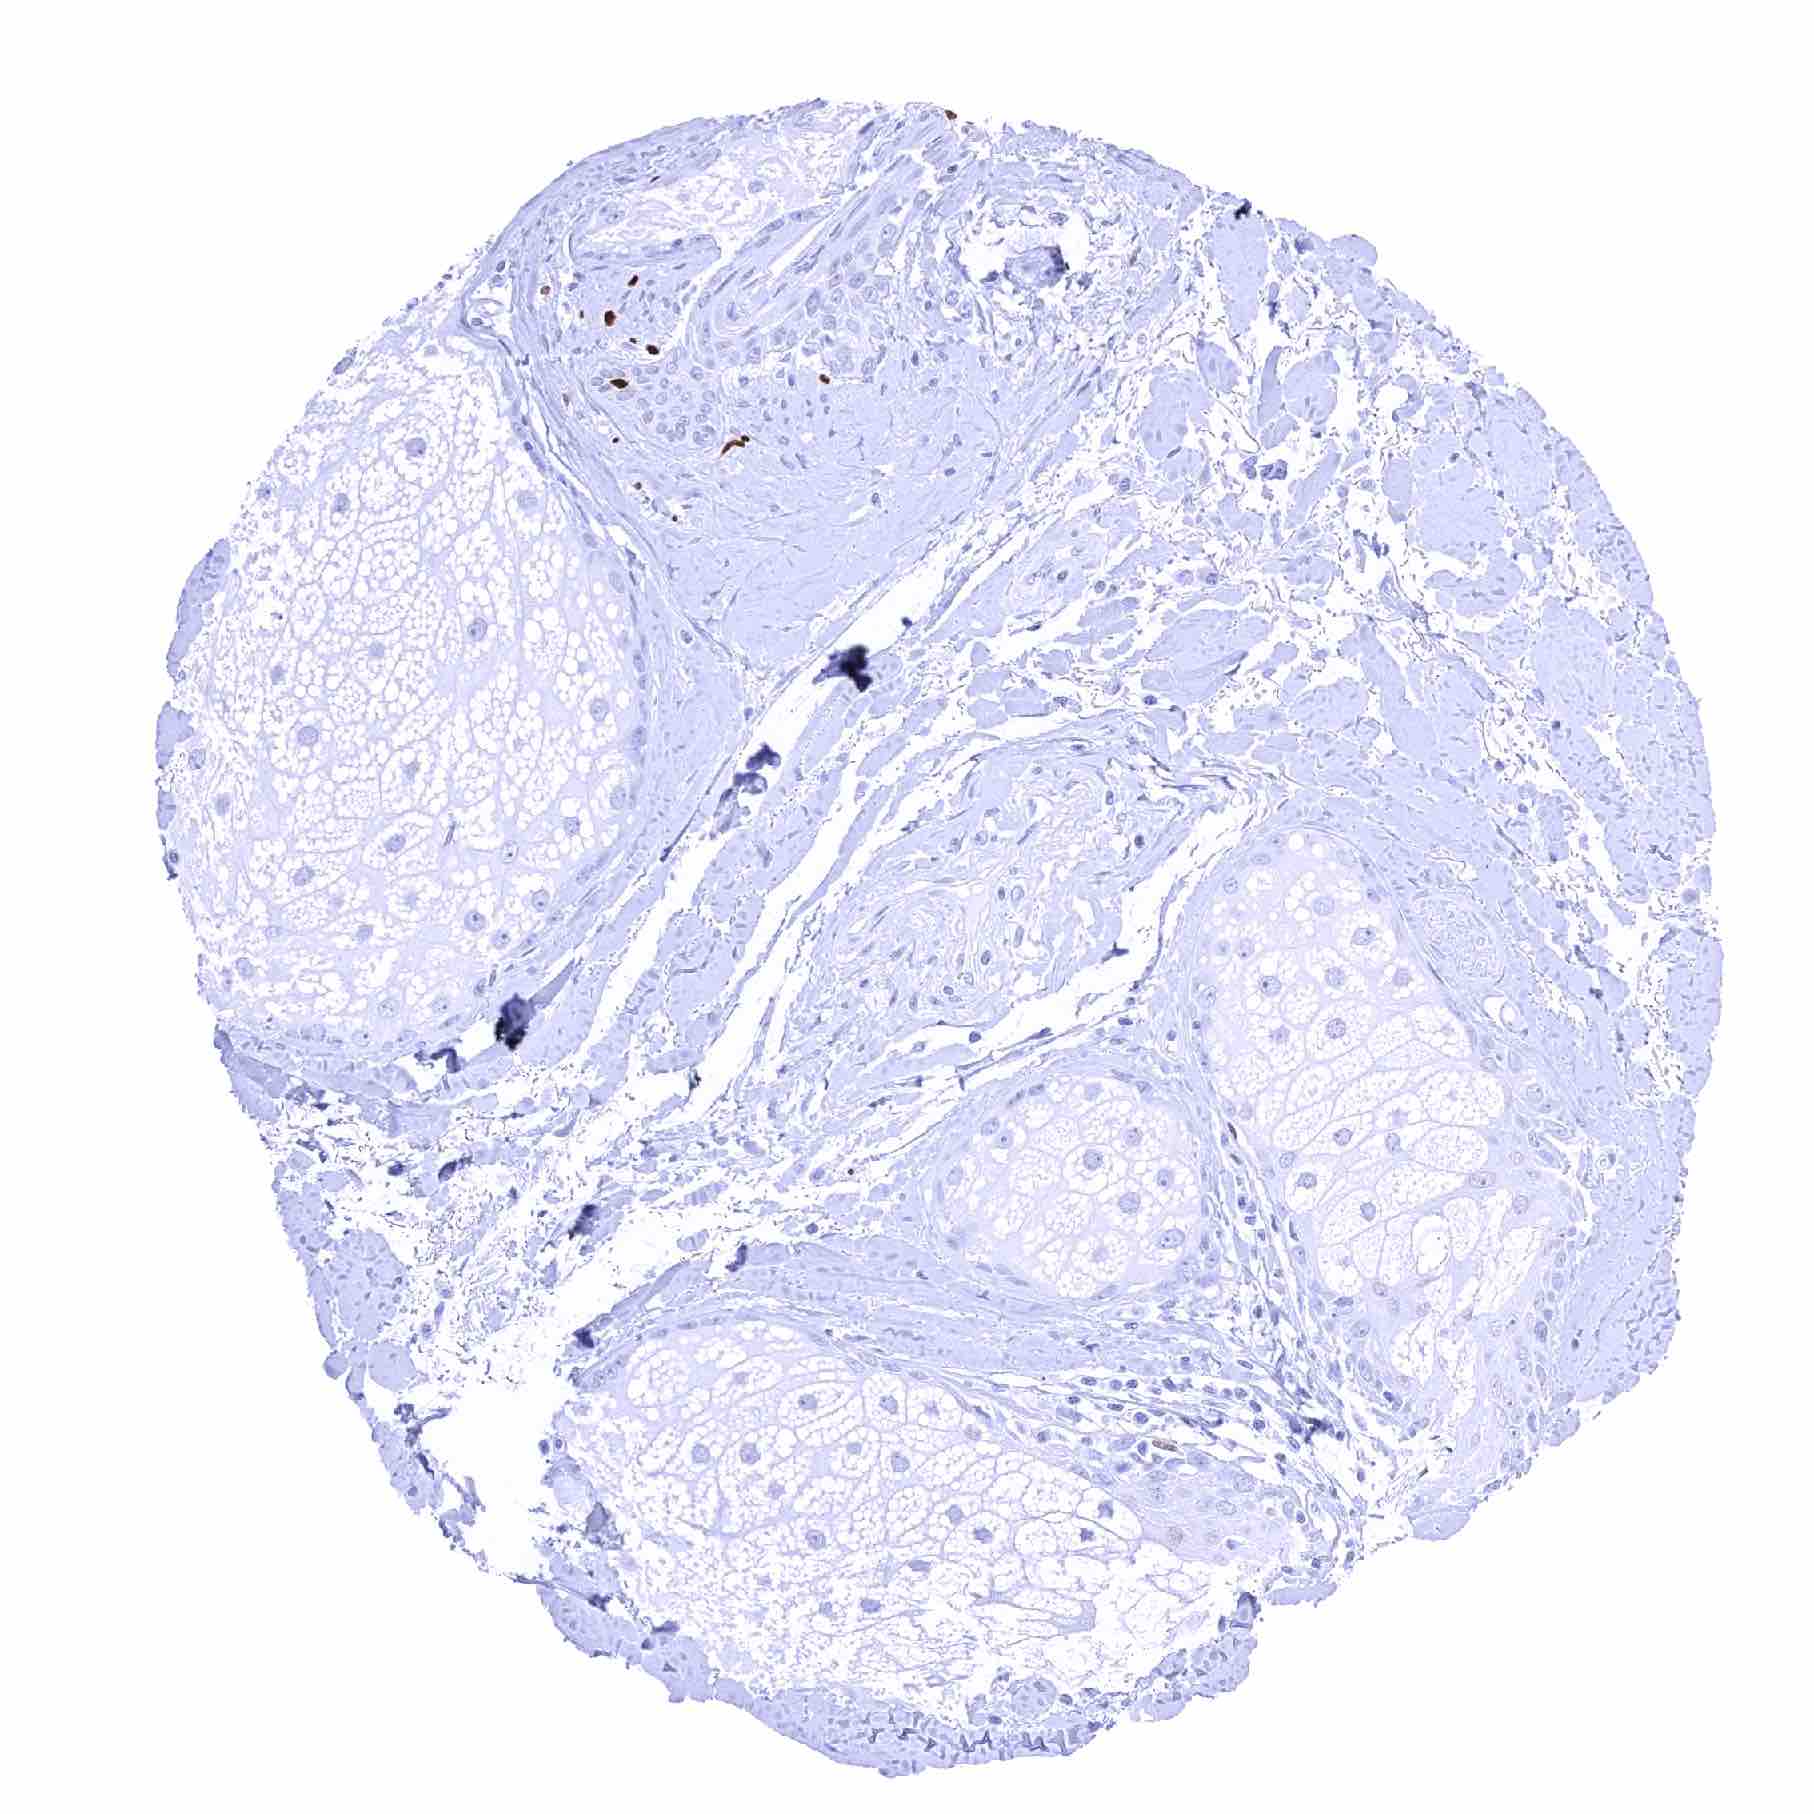

Testis – Weak to moderate SOX2 positivity of spermatocytes